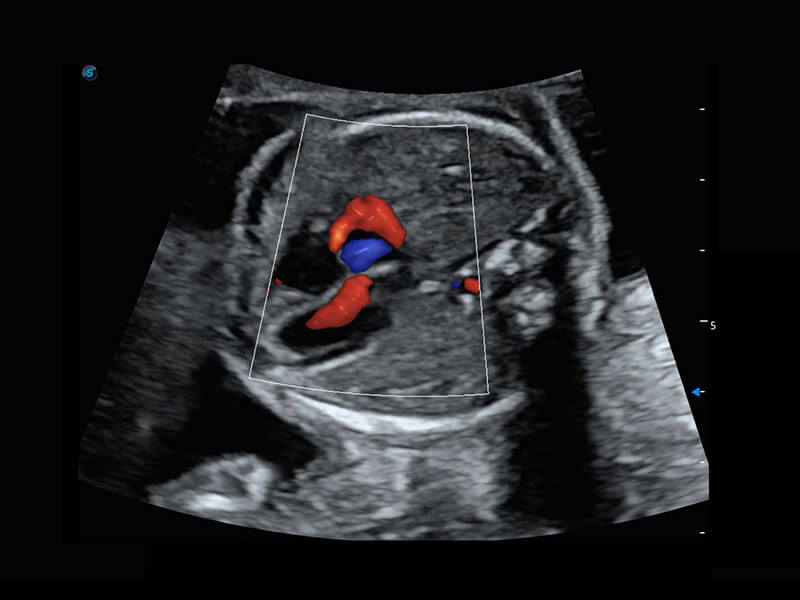

P60搭载一系列胎儿心脏成像技术,实现精细的胎儿心脏评估。

四腔切面

四腔心血流

胎心容积成像